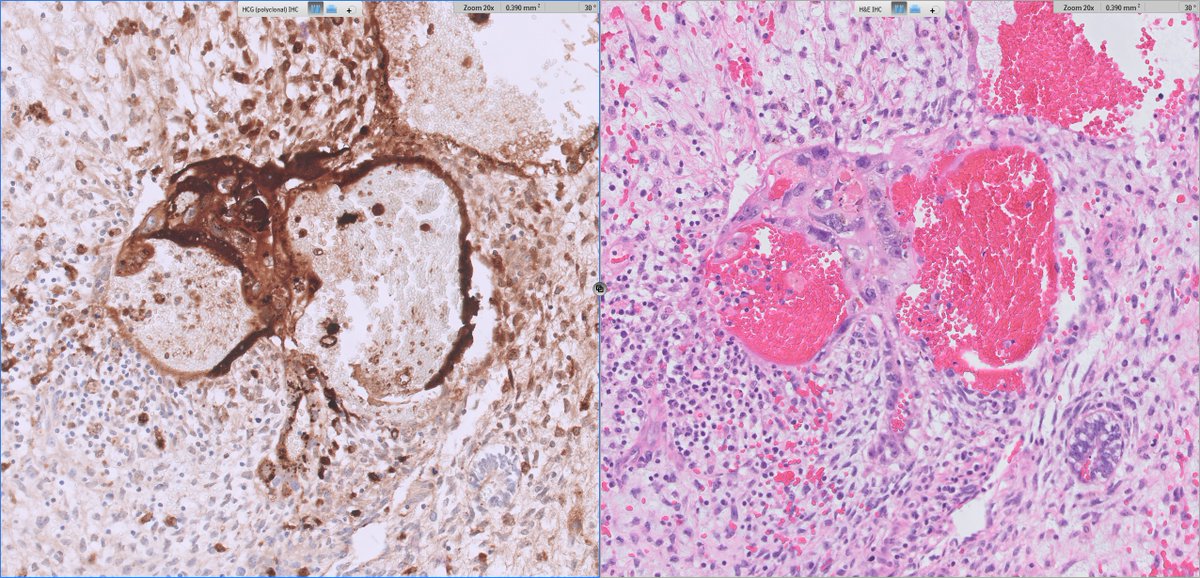

#GUpath orchiectomy:

mixed germ cell tumor (GCT) with admixed syncytiotrophoblasts

✔️may account for low serum elevations of HCG but NOT diagnostic of choriocarcinoma elements

@DanGrahamMD great Q! No minimum quant per say I report any %, as long as it is def chorio (syncytios+admixed cytotrophs; often assoc w/hemm). fortunately, per this paper limited chorio (<5%) likely not prognostic anyhow, but for completeness and to correlate with serum HCG I report any

@slusagar I think I’ve made that mistake of calling a chorio component. So now we gotta know, what’s the minimum required to call it?